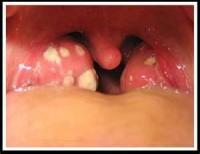

5、   急性咽炎或咽扁桃腺炎:发烧约三至五天,多数是病毒性,如为A族链球菌引起的,用抗生素可缩短发烧时间,有些会并发猩红热或风湿性心脏病。

18. 关於A型链球菌咽喉炎..

A族溶血型链球菌之所以可怕在於其感染后如果没有经过完整的抗生素治疗,经过一段时间后会对肾脏和心脏造成破坏。风湿热是由於罹患A型链球菌咽喉炎一至五周后所引发的全身性免疫发炎反应,包括心脏、关节、脑部及皮肤等器官,其中以心脏的侵犯最为重要。A型链球菌咽喉炎感染后约有百分之三的机会造成风湿热,因此当儿童喉咙痛,喉咙发炎时,家长不可掉以轻心。

一般感染了A型链球菌,十二个钟头到十天左右可能就会出现身体不舒服的现象。大约有百分之十五的病例不会有任何不舒服的情形,不过,这些不会发病的人,仍可以将病菌传给其他人,而引起其他人发病。因此,当怀疑是A型链球菌感染时,全家人都需要小心评估是否亦被感染而需要好好治疗。

取喉咙或皮肤的分泌物作细菌培养是最重要的诊断,不过培养需要三天的时间。除了一些必要的症状治疗如退烧药外,对抗细菌治疗最好的药物就是抗生素。没有抗生素的治疗,会引发心脏与肾脏的并发症,而且一旦有心脏病的出现,治疗是漫长而辛苦的。虽然常常闻「抗生素」色变,此时,却是要确确实时的配合医师的用药,不要自行停药,而发生不可恢复的伤害。